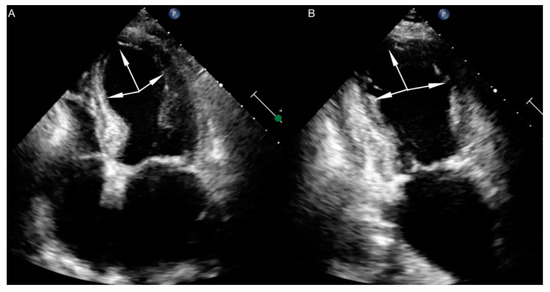

- Opolski, G.; Kochanowski, J.; Torbicki, A.; Scisło, P.; Kowalik, R.; Piotrowska-Kownacka, D.; Zarebiński, M.; Pruszczyk, P.; Kalarus, Z. The recurrence after ten years—“Mother in-law variant” of tako-tsubo syndrome. Kardiol. Pol. 2010, 68, 557–561. [Google Scholar]

- Opolski, G.; Budnik, M.; Kochanowski, J.; Kowalik, R.; Piatkowski, R.; Kochman, J. Four episodes of takotsubo cardiomyopathy in one patient. Int. J. Cardiol. 2016, 203, 53–54. [Google Scholar] [CrossRef]